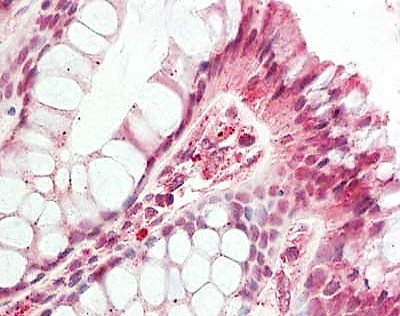

免疫组织化学(IHC)组织样本分析(图2-4)对于检测样本中的蛋白质至关重要,通常用于诊断实验,但不会产生允许共定位实验的图像。

IHC

组织标本用福尔马林固定石蜡包埋固定。蛋白检测采用一抗5µg/mL (HDAC5和HDAC10)或1:500 (HDAC1)室温1 h。二抗:过氧化物酶兔二抗(Rockland, p/n 611-103-122),室温1:10 000孵育45分钟。用苏木精紫或蓝核复染显示蛋白为红色或紫色信号。一抗显示:HDAC1 (Rockland, p/n 600-401-879), HDAC5 (Rockland, p/n 600-401-J69)和HDAC10 (Rockland, p/n 600-401-J75)。

在这里,我们展示了HDAC1在癌组织(图2)和表皮样癌细胞(图5)中的染色。在分析的样本中,HDAC1定位被确认为细胞核。在某些肿瘤样本中未观察到报道的HDAC1的胞浆染色。使用发生的与共焦成像相比,显微镜显示分辨率明显提高(图5)。这些结果清楚地表明,使用适当的经验证抗体和发生的显微镜是研究超越衍射极限的亚细胞结构的重要工具,它可以纠正定义不清的图像。这在细胞内蛋白质共定位研究中至关重要。